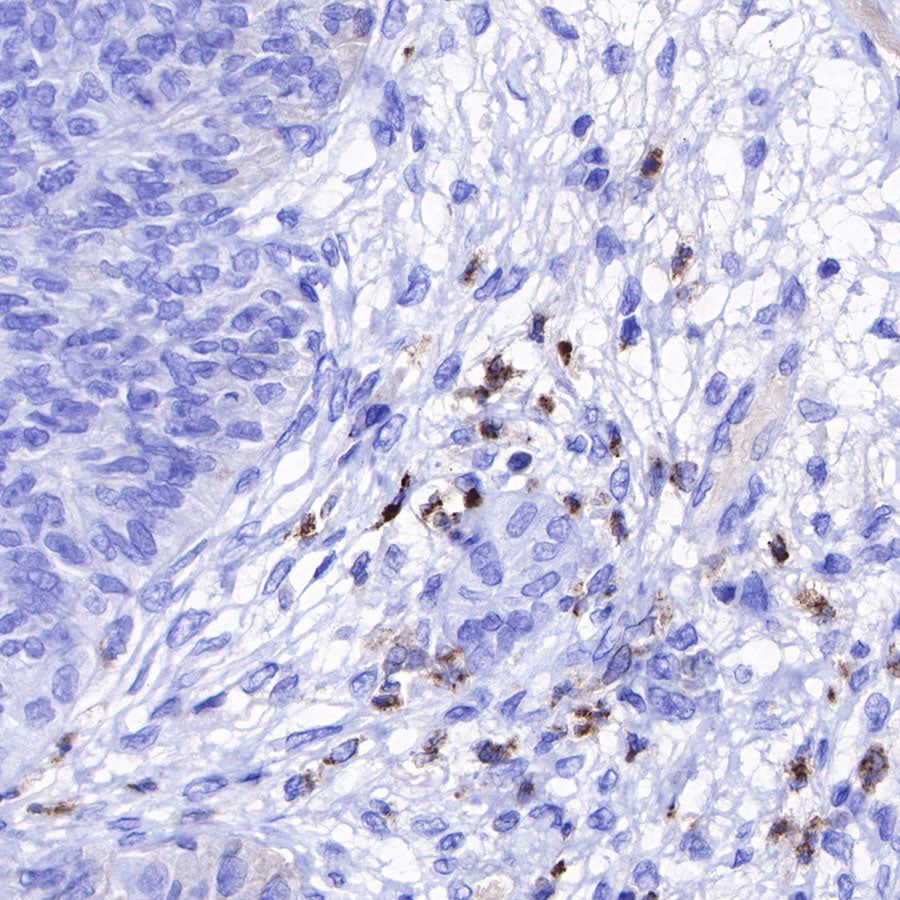

IHC shows positive staining in paraffin-embedded human liver. Anti-Lysozyme antibody was used at 1/100 dilution, followed by a HRP Polymer for Mouse & Rabbit IgG (ready to use). Counterstained with hematoxylin. Heat mediated antigen retrieval with Tris/EDTA buffer pH9.0 was performed before commencing with IHC staining protocol.

IHC shows positive staining in paraffin-embedded human tonsil. Anti-Lysozyme antibody was used at 1/100 dilution, followed by a HRP Polymer for Mouse & Rabbit IgG (ready to use). Counterstained with hematoxylin. Heat mediated antigen retrieval with Tris/EDTA buffer pH9.0 was performed before commencing with IHC staining protocol.

IHC shows positive staining in paraffin-embedded human spleen. Anti-Lysozyme antibody was used at 1/100 dilution, followed by a HRP Polymer for Mouse & Rabbit IgG (ready to use). Counterstained with hematoxylin. Heat mediated antigen retrieval with Tris/EDTA buffer pH9.0 was performed before commencing with IHC staining protocol.

IHC shows positive staining in paraffin-embedded human colon cancer. Anti-Lysozyme antibody was used at 1/100 dilution, followed by a HRP Polymer for Mouse & Rabbit IgG (ready to use). Counterstained with hematoxylin. Heat mediated antigen retrieval with Tris/EDTA buffer pH9.0 was performed before commencing with IHC staining protocol.

IHC shows positive staining in paraffin-embedded human ovarian cancer. Anti-Lysozyme antibody was used at 1/100 dilution, followed by a HRP Polymer for Mouse & Rabbit IgG (ready to use). Counterstained with hematoxylin. Heat mediated antigen retrieval with Tris/EDTA buffer pH9.0 was performed before commencing with IHC staining protocol.

IHC shows positive staining in paraffin-embedded human lung squamous cell carcinoma. Anti-Lysozyme antibody was used at 1/100 dilution, followed by a HRP Polymer for Mouse & Rabbit IgG (ready to use). Counterstained with hematoxylin. Heat mediated antigen retrieval with Tris/EDTA buffer pH9.0 was performed before commencing with IHC staining protocol.

IHC shows positive staining in paraffin-embedded human endometrial carcinoma. Anti-Lysozyme antibody was used at 1/100 dilution, followed by a HRP Polymer for Mouse & Rabbit IgG (ready to use). Counterstained with hematoxylin. Heat mediated antigen retrieval with Tris/EDTA buffer pH9.0 was performed before commencing with IHC staining protocol.